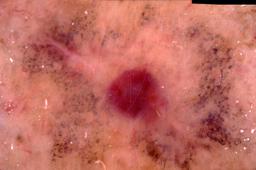

{

"age_approx": 70,

"anatom_site_general": "head/neck",

"concomitant_biopsy": true,

"dermoscopic_type": "contact non-polarized",

"diagnosis_1": "Indeterminate",

"diagnosis_2": "Indeterminate epidermal proliferations",

"diagnosis_3": "Solar or actinic keratosis",

"diagnosis_4": "Actinic keratosis, Lichenoid",

"diagnosis_confirm_type": "histopathology",

"image_type": "dermoscopic",

"lesion_id": "IL_5320579",

"patient_id": "IP_4936244",

"sex": "male"

}